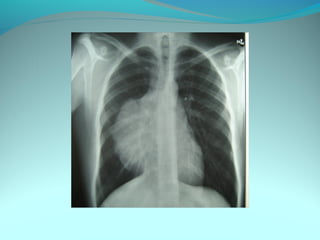

Opacité occupant la partie externe du 1/3 infer du poumon droit

dense et homogene ovalaire de 8cm de grand axe vertical

La limite externe se confend avec une opacité d’environ 1cm comble

les coupole costodiaphragmatique droit

Limitée a sa partie sup par la petit sessure qui est epaisse et pas de

lyse costale

 DIAGNOSTIC :DIAGNOSTIC :

 1_1_cancer bronchique droit( d epaississement)

 2_2_ kyste hydatique au stade sain